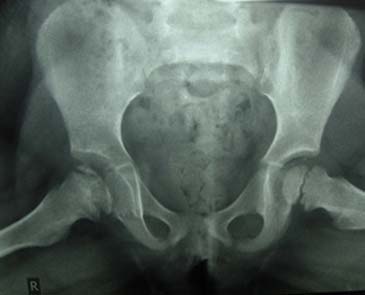

Οστεοχονδρίτιδα μηριαίας κεφαλής - Νόσος Parthes

Εικόνα Οστεοχονδρίτιδα δεξιάς μηριαίας επίφυσης, στο στάδιο κατακερματισμού